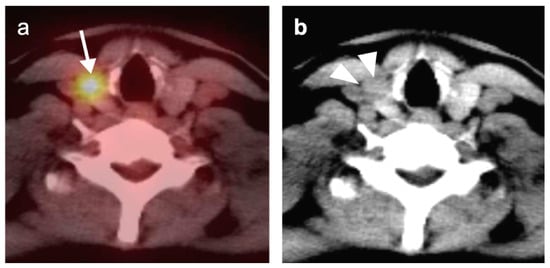

2.6. Thyroid Cancer

- Differentiated thyroid cancer

- 3.